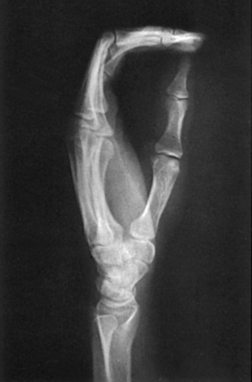

Structures shown: This image, which shows a lateral projection of the hand in extension (Fig. 4-62), is the customary position for localizing foreign bodies and metacarpal fracture displacement. The exposure technique depends on the foreign body.

The fan lateral superimposes the metacarpals but shows almost all of the individual phalanges. The most proximal portions of the proximal phalanges remain superimposed (Fig. 4-63).

This projection is useful when a hand injury prevents the patient from extending the fingers.

• With the patient relaxing the digits to maintain the natural arch of the hand, arrange the digits so that they are perfectly superimposed (Fig. 4-64).

Structures shown: This projection produces a lateral image of the bony structures and soft tissues of the hand in their normally flexed position (Fig. 4-65). It also shows anterior or posterior displacement in fractures of the metacarpals.